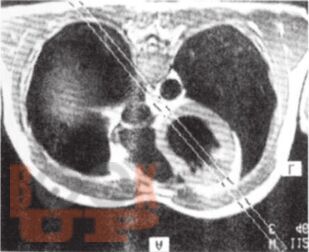

В книге всемирно известных авторов детально представлены вопросы применения электрокардиографии при инфаркте миокарда с подъемом ST. Предложенный авторами революционный подход к интерпретации стандартной ЭКГ в 12 отведениях позволяет не только констатировать наличие инфаркта и определить его локализацию, но с большой точностью установить, окклюзия какой коронарной артерии и на каком уровне произошла и какие сегменты миокарда оказались вовлечены в патологический процесс. Это существенно расширяет потенциал ЭКГ в современных условиях широкого применения методов интервенционной кардиологии и кардиохирургии, а также увеличивает прогностические возможности электрокардиографии при остром инфаркте миокарда.